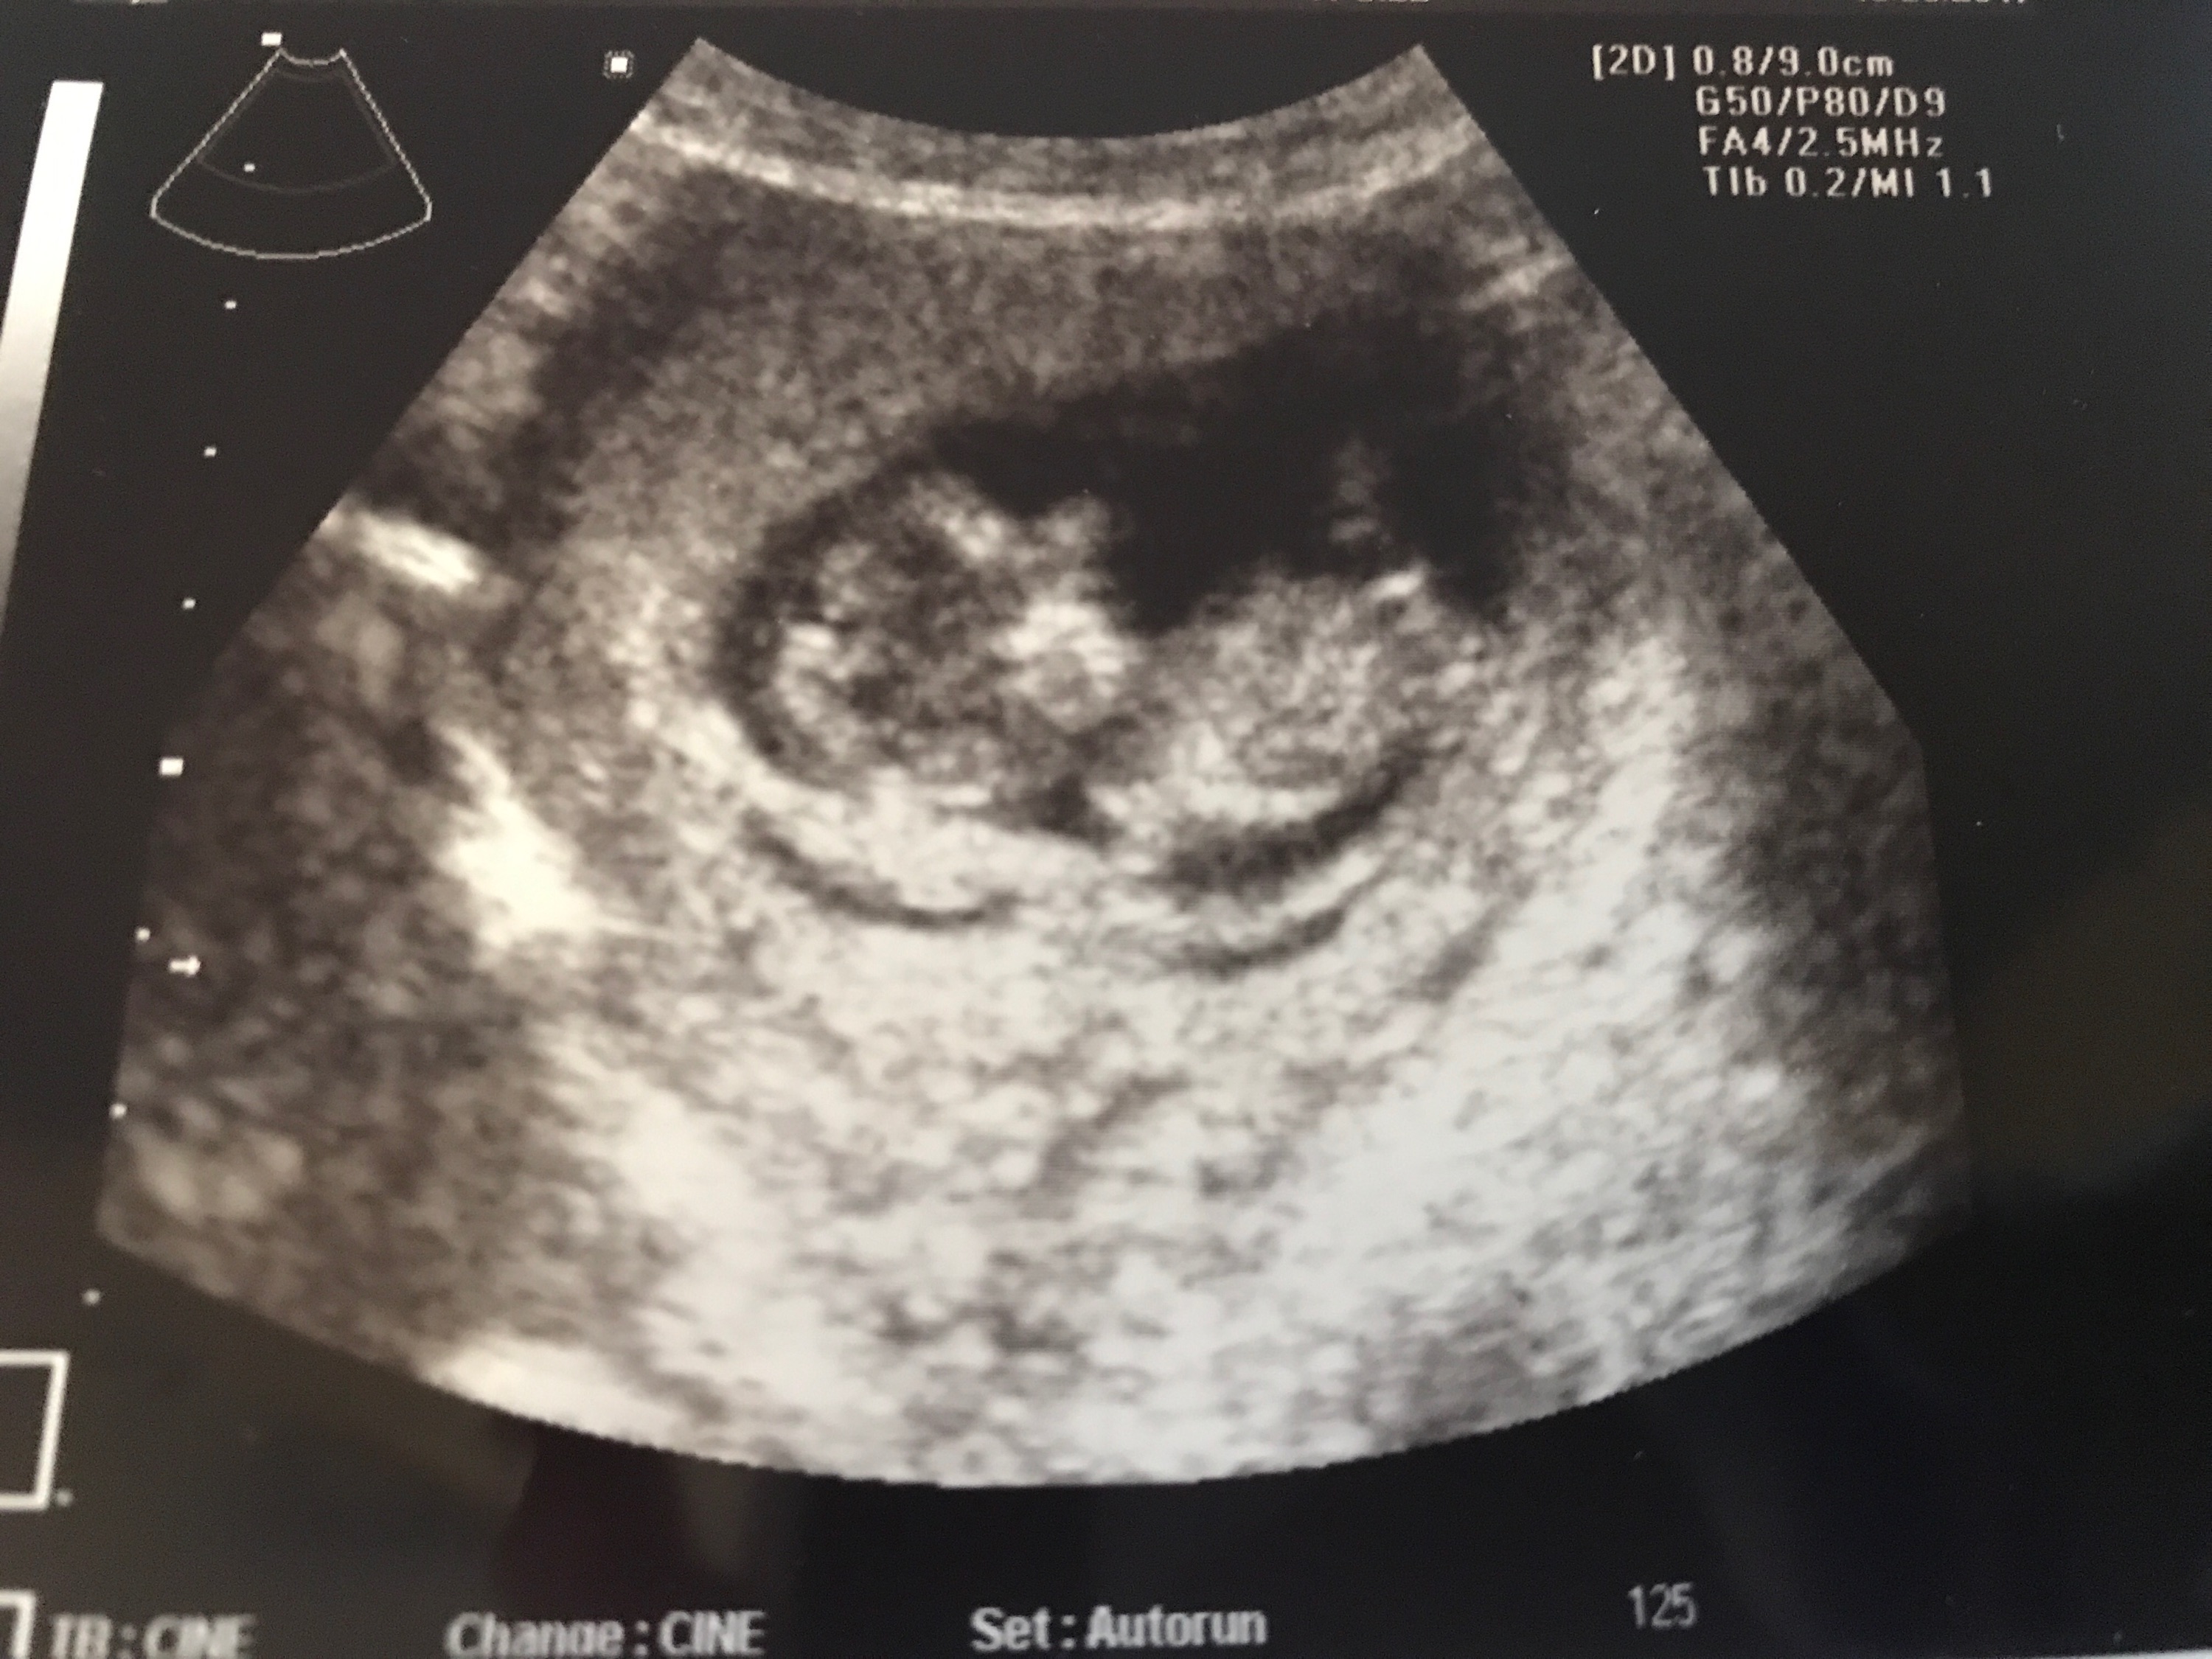

I know it’s not an ideal time, a bit early, but please give your guesses.....Attachment 38031

I'll give very tentative pink guess but please don't put any stock into it at all, it's really not the type of pic that is at all good for guessing - gestation, the baby's curled up, and it's grainy.